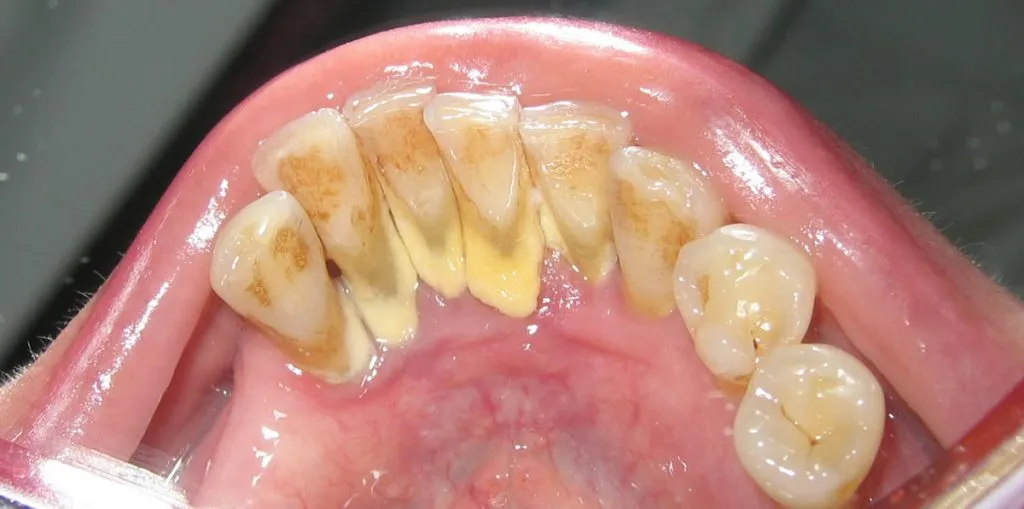

Obecność kamienia nazębnego ma znaczący wpływ na estetykę uśmiechu. Zęby pokryte kamieniem wyglądają na żółte lub brązowe, co może negatywnie wpływać na pewność siebie osoby. Kamień nazębny tworzy nieestetyczne osady, które są trudne do usunięcia domowymi metodami. Osoby z nagromadzonym kamieniem często czują się niekomfortowo przy uśmiechu, co może prowadzić do unikania sytuacji społecznych. Dlatego tak ważne jest, aby dbać o higienę jamy ustnej, aby uniknąć problemów estetycznych związanych z kamieniem.

| Typ zębów | Wygląd zębów czystych | Wygląd zębów z kamieniem |

|---|---|---|

| Zęby przednie | Śnieżnobiały kolor, gładka powierzchnia | Żółtawe lub brązowe plamy, nierówności |

| Zęby tylne | Gładkie, czyste | Widoczne osady, matowy wygląd |

| Zęby trzonowe | Zdrowe, błyszczące | Przebarwienia, osady, trudności w czyszczeniu |